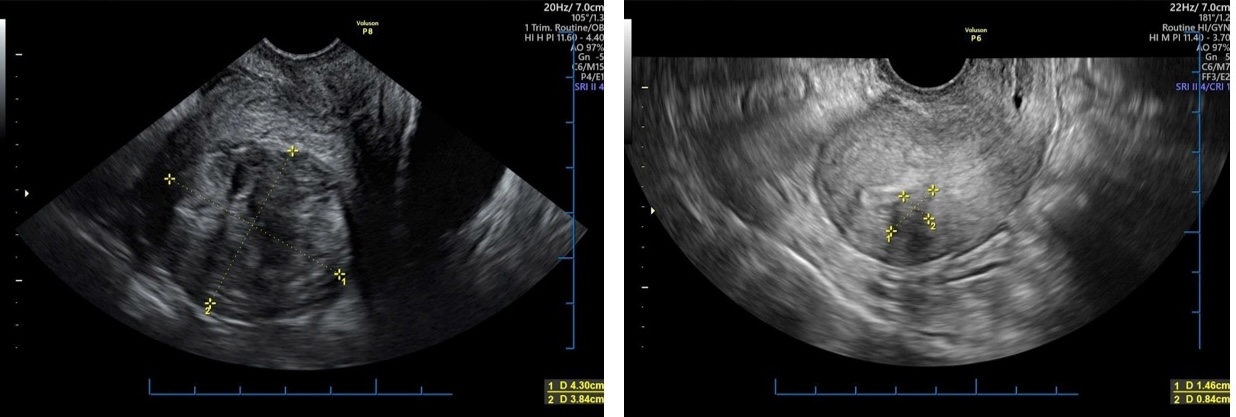

U xơ tử cung, trước (ảnh trái) và sau điều trị bằng US-HIFU

Điều trị bằng phẫu thuật từng được xem là giải pháp chủ yếu, nhưng phương pháp này thường để lại sẹo, nguy cơ biến chứng và có thể ảnh hưởng đến khả năng sinh sản. Hiện US-HIFU là phương pháp điều trị hiện đại, mang lại hiệu quả vượt trội trong việc loại bỏ khối u phụ khoa mà không gây tổn thương mô lành. Với ưu điểm bảo tồn tử cung và khả năng sinh sản, đây là giải pháp an toàn, phù hợp cho nhiều phụ nữ, đặc biệt là những người còn mong muốn có con.

GS-TS Nguyễn Viết Tiến cho biết, US-HIFU (High Intensity Focused Ultrasound) là phương pháp sử dụng sóng siêu âm hội tụ chính xác vào khối u, tạo nhiệt độ cao tại vùng bệnh để phá hủy mô bệnh lý. Khác với phẫu thuật truyền thống, US-HIFU không cần rạch mổ, không gây chảy máu, đồng thời hạn chế tối đa ảnh hưởng đến mô lành.

GS Tiến đánh giá, kỹ thuật US-HIFU có ưu điểm nổi bật: an toàn, không xâm lấn, không để lại sẹo, giảm nguy cơ nhiễm trùng; giúp giảm hoặc loại bỏ hoàn toàn khối u. Thời gian hồi phục nhanh, người bệnh có thể trở lại sinh hoạt bình thường chỉ sau vài ngày; ít đau, không cần gây mê toàn thân. Đặc biệt, bảo tồn khả năng sinh sản là ưu điểm vượt trội.